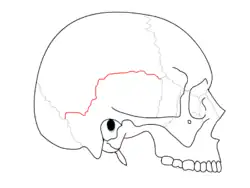

Trauma

Temporal bone fractures were historically divided into three main categories, longitudinal, in which the vertical axis of the fracture paralleled the petrous ridge, horizontal, in which the axis of the fracture was perpendicular to the petrous ridge, and oblique, a mixed type with both longitudinal and horizontal components. Horizontal fractures were thought to be associated with injuries to the facial nerve, and longitudinal with injuries to the middle ear ossicles.[6] More recently, delineation based on disruption of the otic capsule has been found as more reliable in predicting complications such as facial nerve injury, sensorineural hearing loss, intracerebral hemorrhage, and cerebrospinal fluid otorrhea.[7]